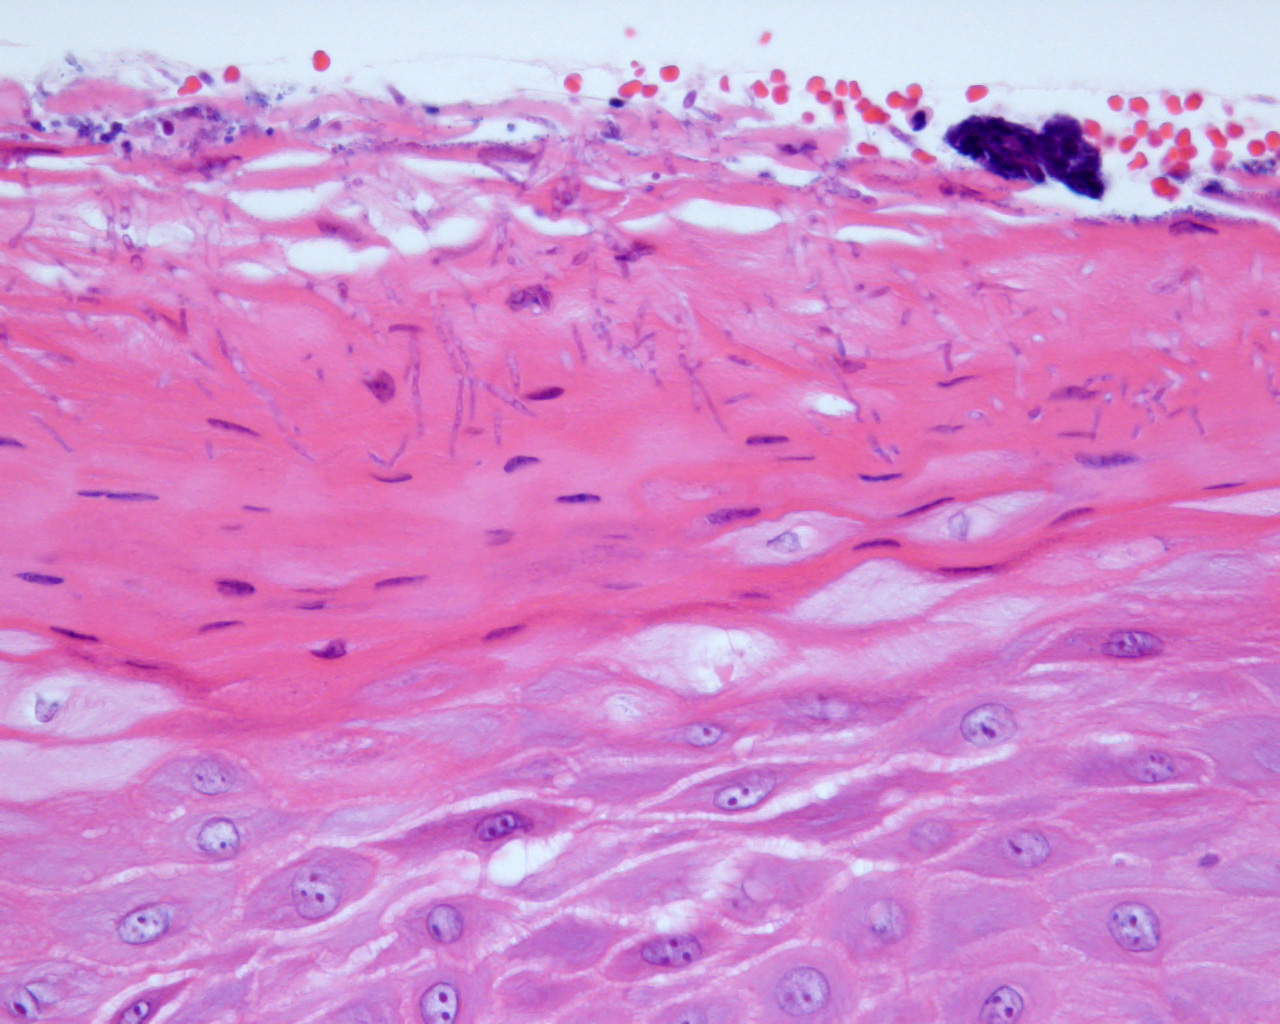

一方でドライマウス、舌痛症、三叉神経痛、顎関節症、口臭症、口腔扁平苔癬、口腔カンジダ症、口腔異常感症など無手術で治療する病気を担当する診療科を口腔内科といいます。従来は専ら口腔外科で対応し

ていたこれらの病気も、今では専門化が進んで担当が分かれています。